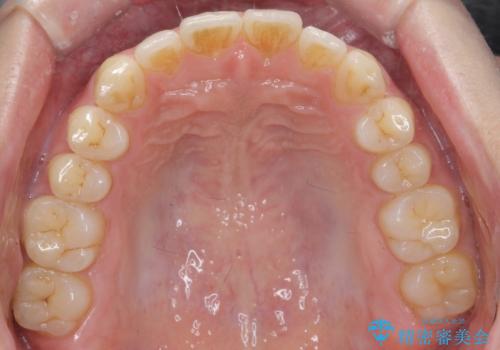

前歯が気になる。インビザラインライト

- 前歯が気になるとの事で来院。

矯正を希望されたが費用と時間を抑えたいとの事でインビザラインライトで矯正を行いました。(奥歯の位置関係はほぼ変えない)

前歯が綺麗に並び大変満足して頂けました。